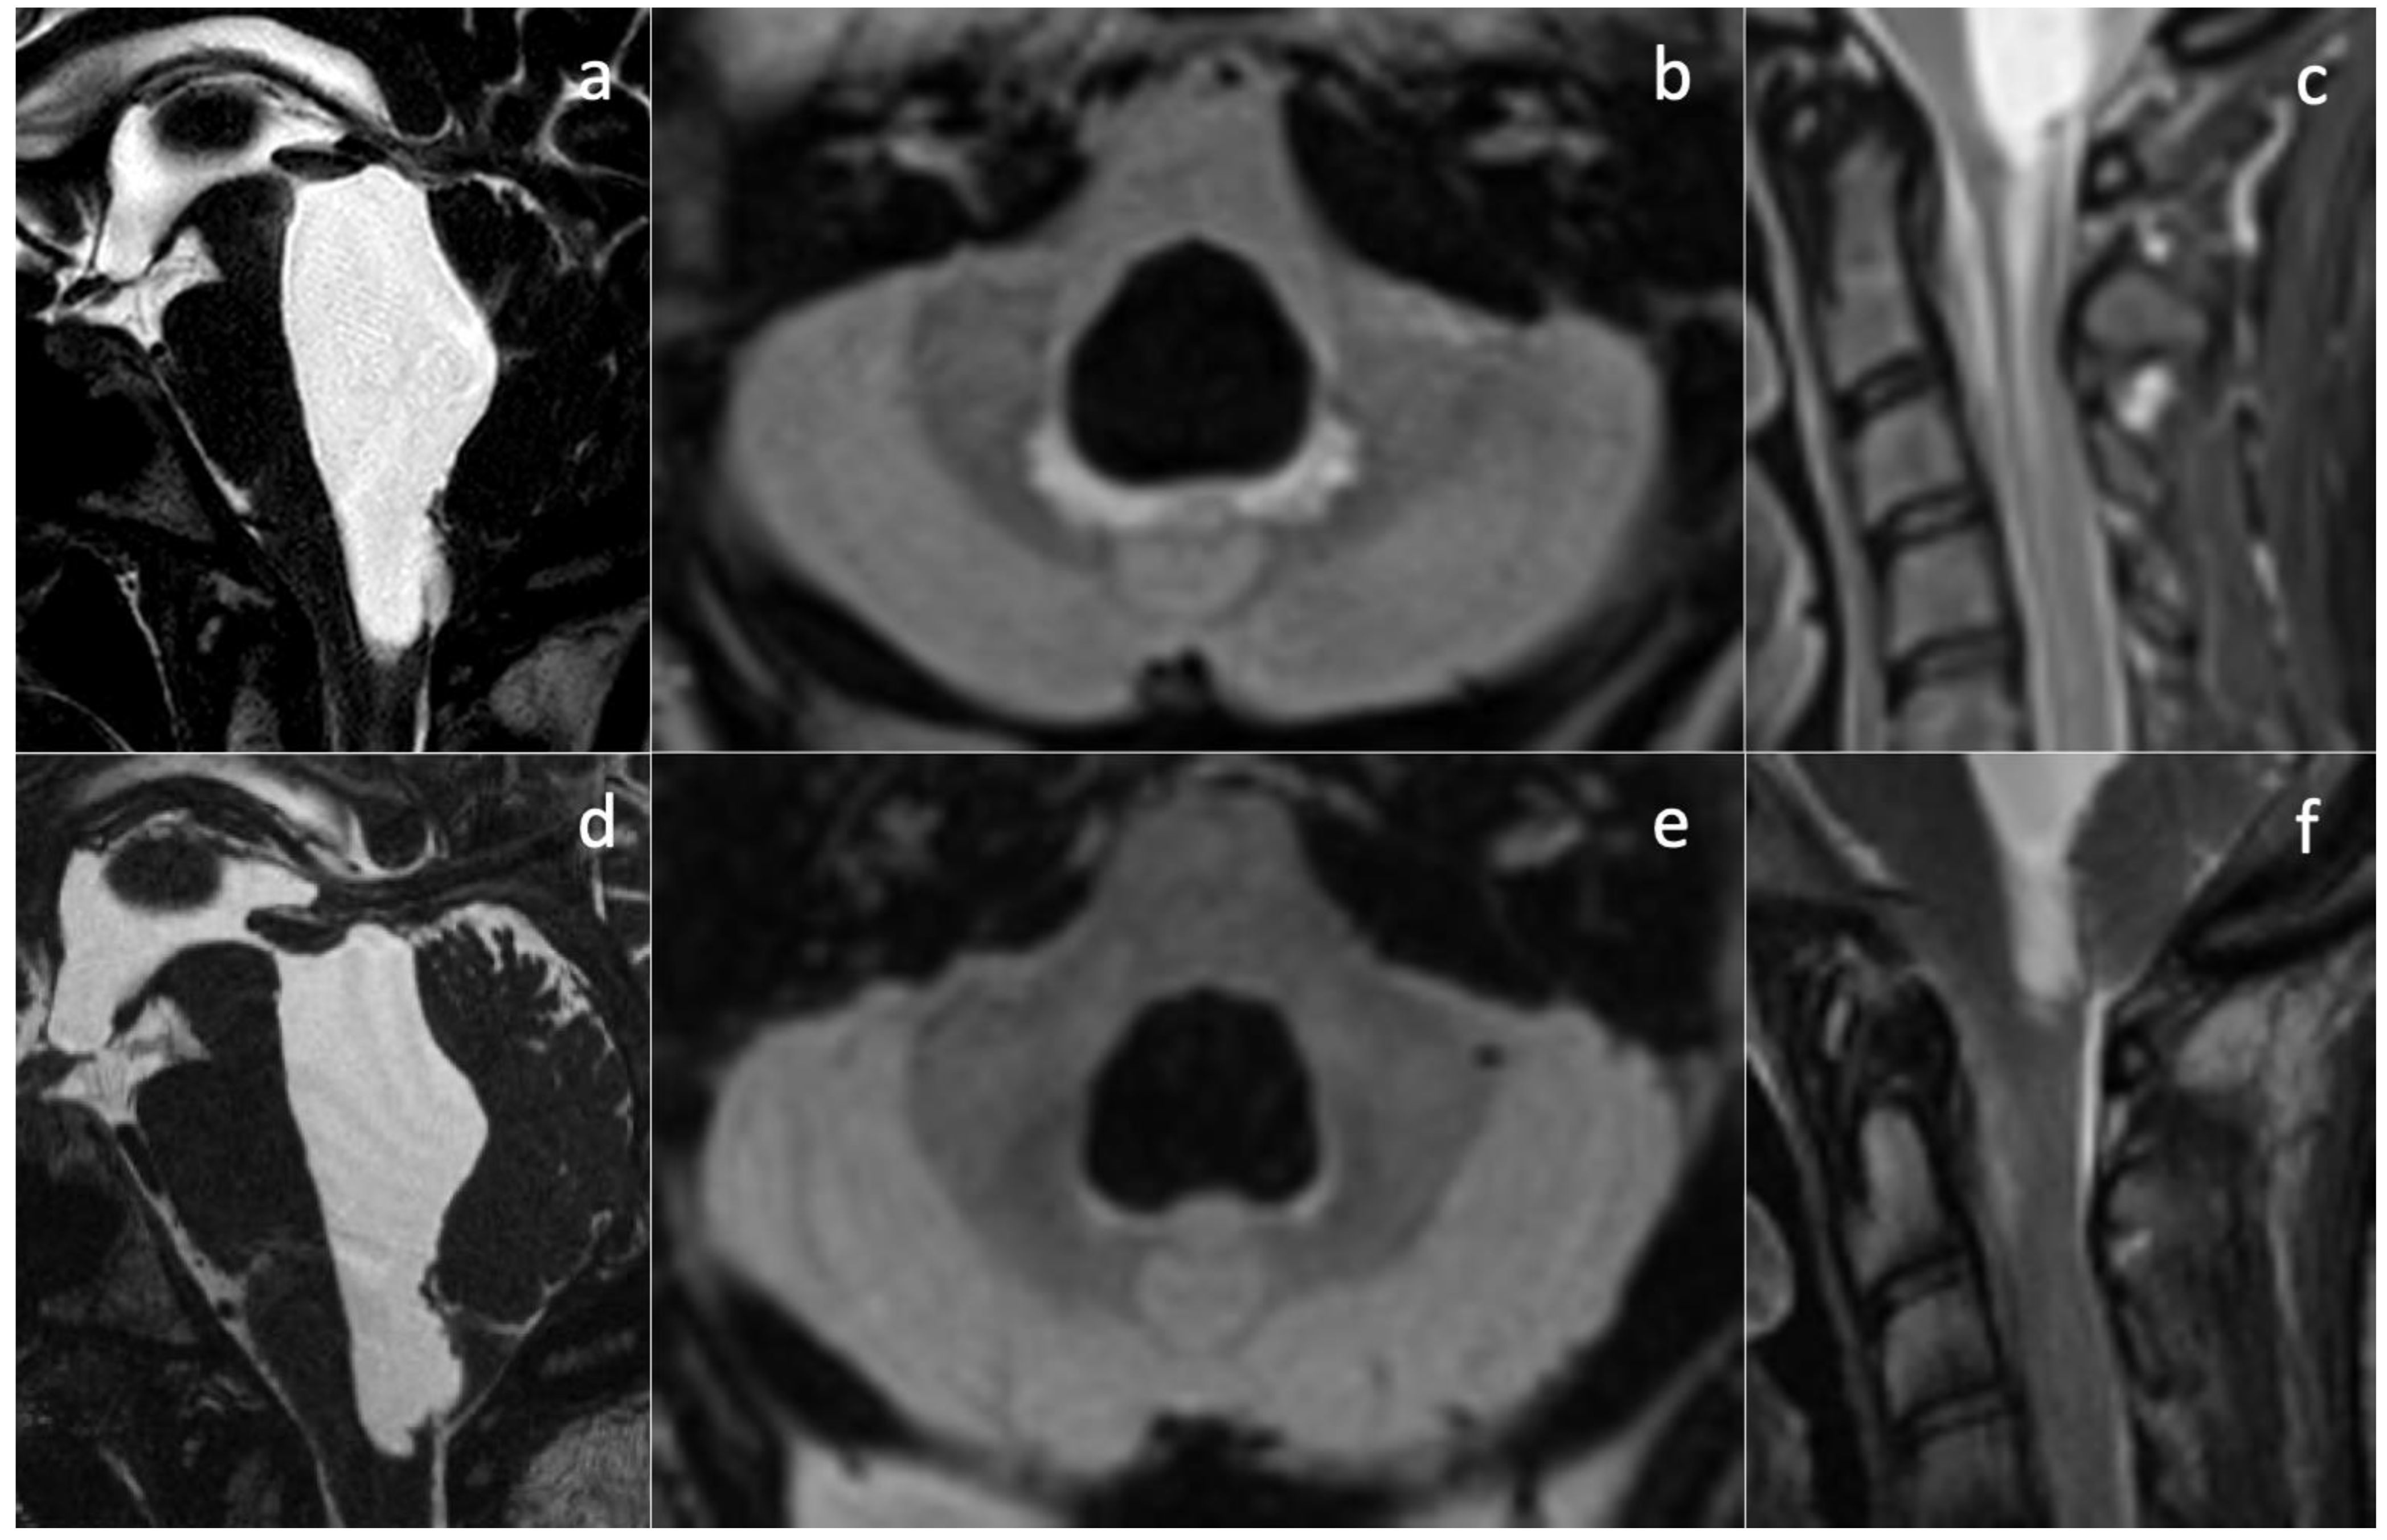

Upon her admission to our hospital, an MRI exam was repeated with contrast media administration. On T2WI, the fourth ventricle was markedly enlarged (Figure 3a and Figure 4a), compressing the pons anteriorly and the cerebellum posteriorly. Accordingly, subtentorial cisterns were effaced. A thin diaphragm was appreciable within the acqueductus Silyii. Axial scans of the enlarged fourth ventricle showed patent and enlarged foramina of Luschka (Figure 3a). T2W hyperintensities in the ventricle walls and around the cranial portion of the central canal suggested trans-ependymal reabsorption and incipient hydromyelia (Figure 4b,c). The MRI exam showed caudal dislocation of the bulbo-medullary junction and herniation of cerebellar tonsils through the foramen magnum. On the other hand, T1W C+ scans showed a diffuse enhancement of the thickened dura mater, surrounded by hyperintense epidural spaces (Figure 4b).

The patient was then diagnosed with isolated dilatation of the fourth ventricle, caused by overdrainage from the SPS causing downward tonsillar displacement as the origin of IV ventricle intracranial and spinal hydrocephalus. The increase in the SPS valve-opening pressure, with subsequent downregulation of the shunt, led to prompt symptom regression and the disappearance of hydromyelia and other MRI signs of trans-ependymal reabsorption (Figure 4e,f).

Isolated dilatation of the fourth ventricle is a rare complication of ventriculoperitoneal shunt surgery, with it being most frequent among pediatric patients and poorly characterized in adults [16,17]. Necessary conditions are, typically, obstruction of the foramina of Luschka and Magendie, inferiorly, and the aqueduct of Sylvius, superiorly. In our case, congenital aqueductal stenosis was present (Figure 4a,d), but foramina were apparently patent—even symmetrically dilated (Figure 3a), while the site of obstruction was farther below. SPS overdrainage caused brainstem and tonsillar sagging, foramen magnum obstruction, and CSF flow trapping in the posterior fossa. Thus, the central canal became the only outflow route available, communicating with the high-pressure closed compartment of the fourth ventricle. Below the foramen magnum, a radial pressure gradient was present from the central canal (abnormally increased pressure) to the spinal subarachnoid space (abnormally decreased pressure). Conspicuous trans-ependymal reabsorption was then provoked in the spinal cord (Figure 4c), at risk of further extension with involvement of the brainstem. The therapeutic approach consisted of only modifying the drainage pressure of the shunt, thus increasing peri-medullary space pressure to normal levels and removing the CSF trapping in the posterior fossa. In turn, this reduced the pressure in the fourth ventricle and removed the gradient established between the central canal and the medullary sub-arachnoid space. The patient’s symptoms rapidly alleviated, without more invasive interventions being required. In subsequent MR examinations, further ascent of cerebellar tonsils was observed, with further resolution of fourth ventricle isolation. Nevertheless, long-term follow-up is needed to monitor the occurrence of late complications, including relapse of overdrainage with spinal subarachnoid space compartmentalization.

Figure 4. Effect of SPD revision on imaging findings. Isolated dilatation of the fourth ventricle is visible before (a) and after drainage downregulation (d). Partial re-expansion of subtentorial cisternal spaces can be seen. A subtle membrane is responsible for the obstruction of the cerebral aqueduct. Signs of peri-ventricular trans-ependymal reabsorption (b) and hydromyelia (c) disappear after shunt revision ((e,f), respectively).